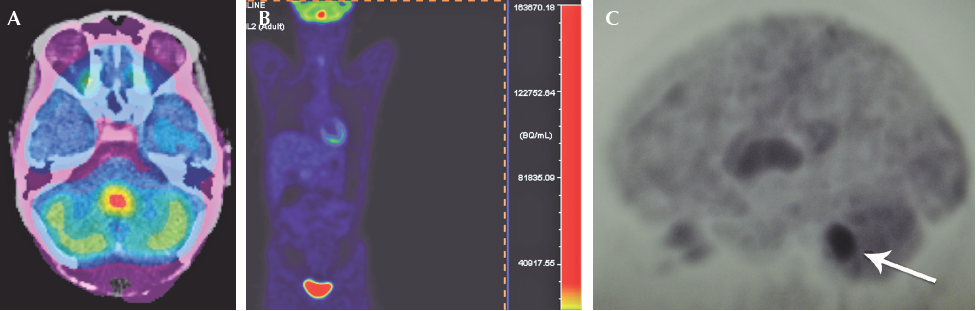

La tomografía por emisión de positrones con fluorodesoxiglucosa mostró una lesión infraten-torial hiperdensa de 15x11 mm localizada en el cuarto ventrículo, con aumento de la actividad glucolítica y valor máximo estandarizado de captación (SUVmáx) de hasta 12.7. El resto del rastreo fue normal (Figura 4).

Figura 4 Tomografía por emisión de positrones. A) Reconstrucción axial: aumento de metabolismo SUVmáx 12.7. B) Proyección cuerpo entero con aumento del metabolismo en fosa posterior, eliminación normal del marcador radioactivo en la vejiga urinaria. C) Proyección sagital del cráneo: aumento del metabolismo en fosa posterior (flecha).